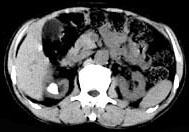

问题 男,53岁,反复右侧腰部隐痛不适2年余,CT如图所示,下列说法正确的是 ( )

选项 A、右肾自截 B、部分肾盏有扩张积液 C、右肾铸型结石 D、右肾钙化 E、右肾多发结石

答案 BCE